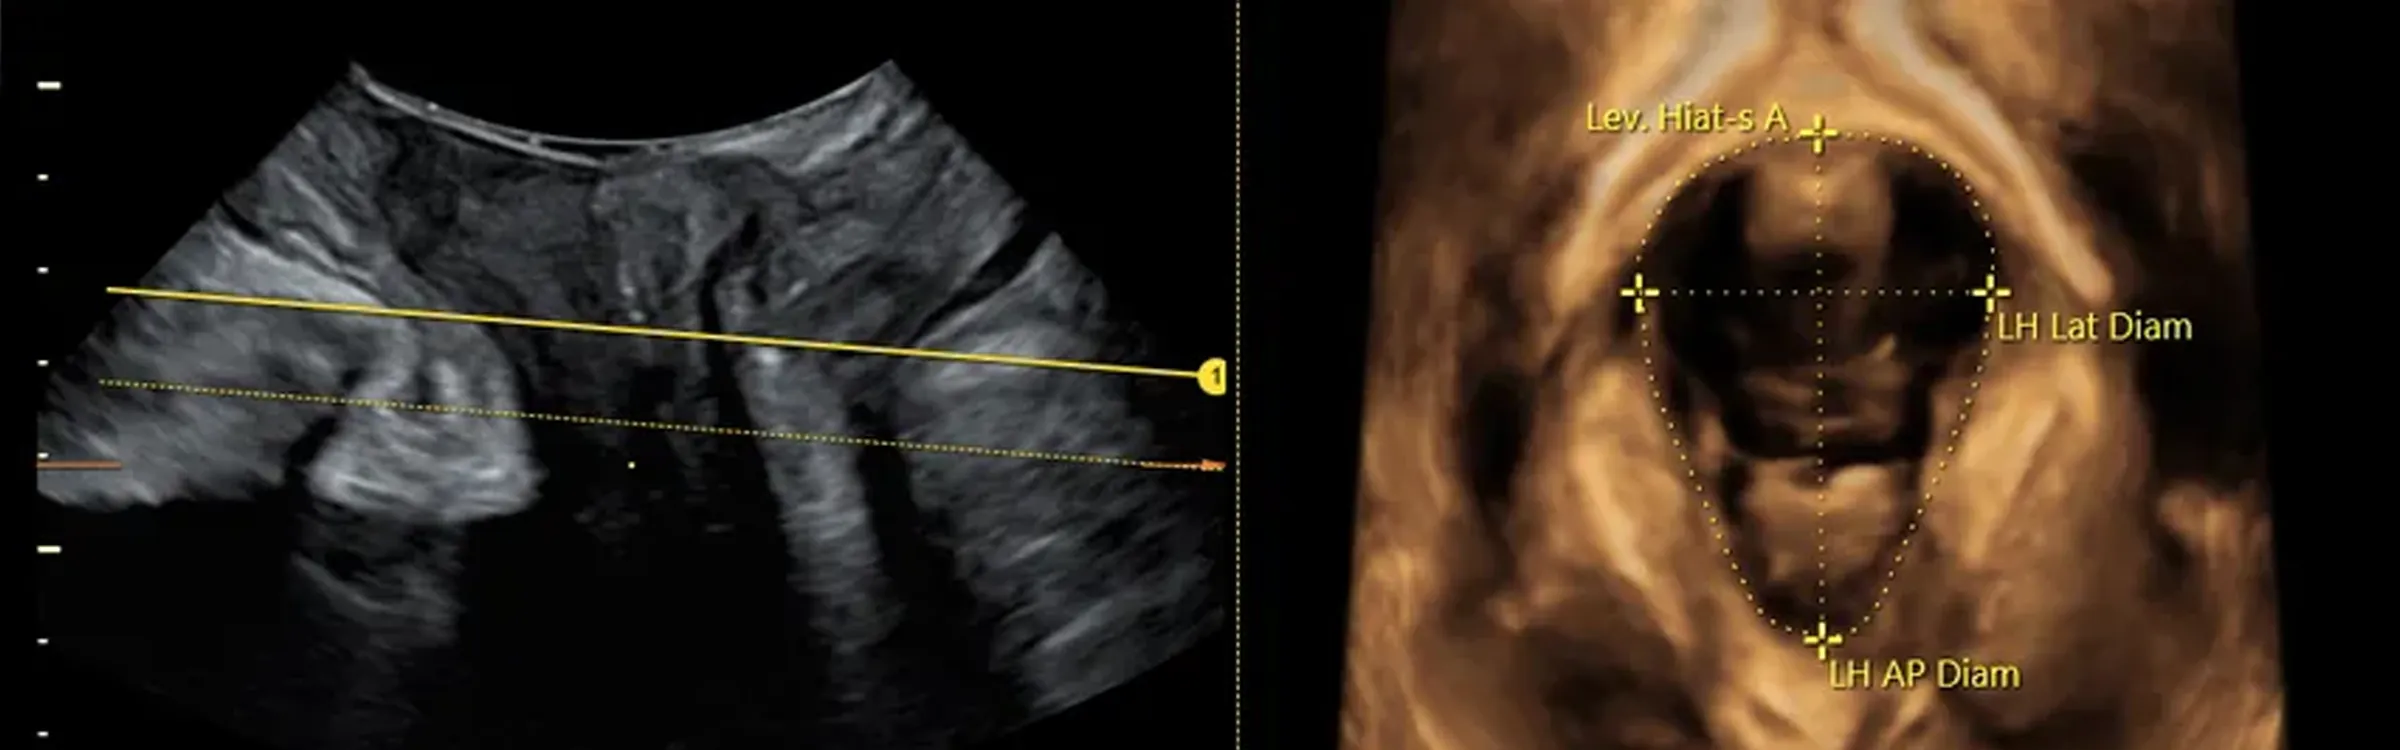

High-resolution imaging, 3D and 4D imaging and the eM6C, the unique electronic volume probe, provide medical professionals with a deeper understanding of the fetal heart. The heart itself and surrounding structures can be imaged and modelled accurately and quickly, helping eliminate complexity and providing real-time visual data.